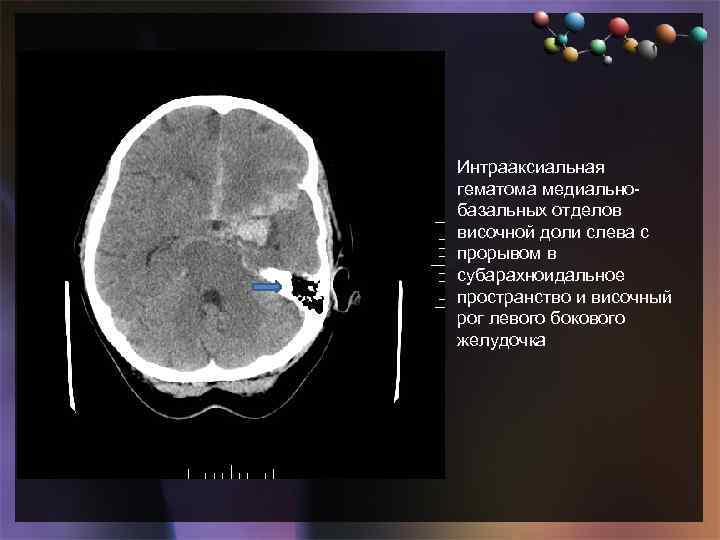

• Подзаголовок слайда Интрааксиальная гематома медиальнобазальных отделов височной доли слева с прорывом в субарахноидальное пространство и височный рог левого бокового желудочка

• Подзаголовок слайда Интрааксиальная гематома медиальнобазальных отделов височной доли слева с прорывом в субарахноидальное пространство и височный рог левого бокового желудочка